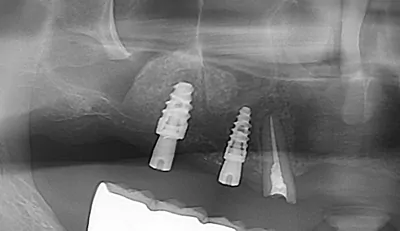

ソケットリフト

歯が生えていた部分、または抜歯後の穴からアプローチする方法で、骨の厚みがある程度残っている場合に適用されます。専用の器具を用いて上顎洞の底を少しずつ押し上げ、できた空間に骨補填材を充填します。その後、同時にインプラントを埋入できるケースもあります。処置が比較的シンプルで腫れや痛みも少なく、治療期間も短め(約4ヶ月)というメリットがありますが、対応できるのは単独の歯の欠損に限られます。